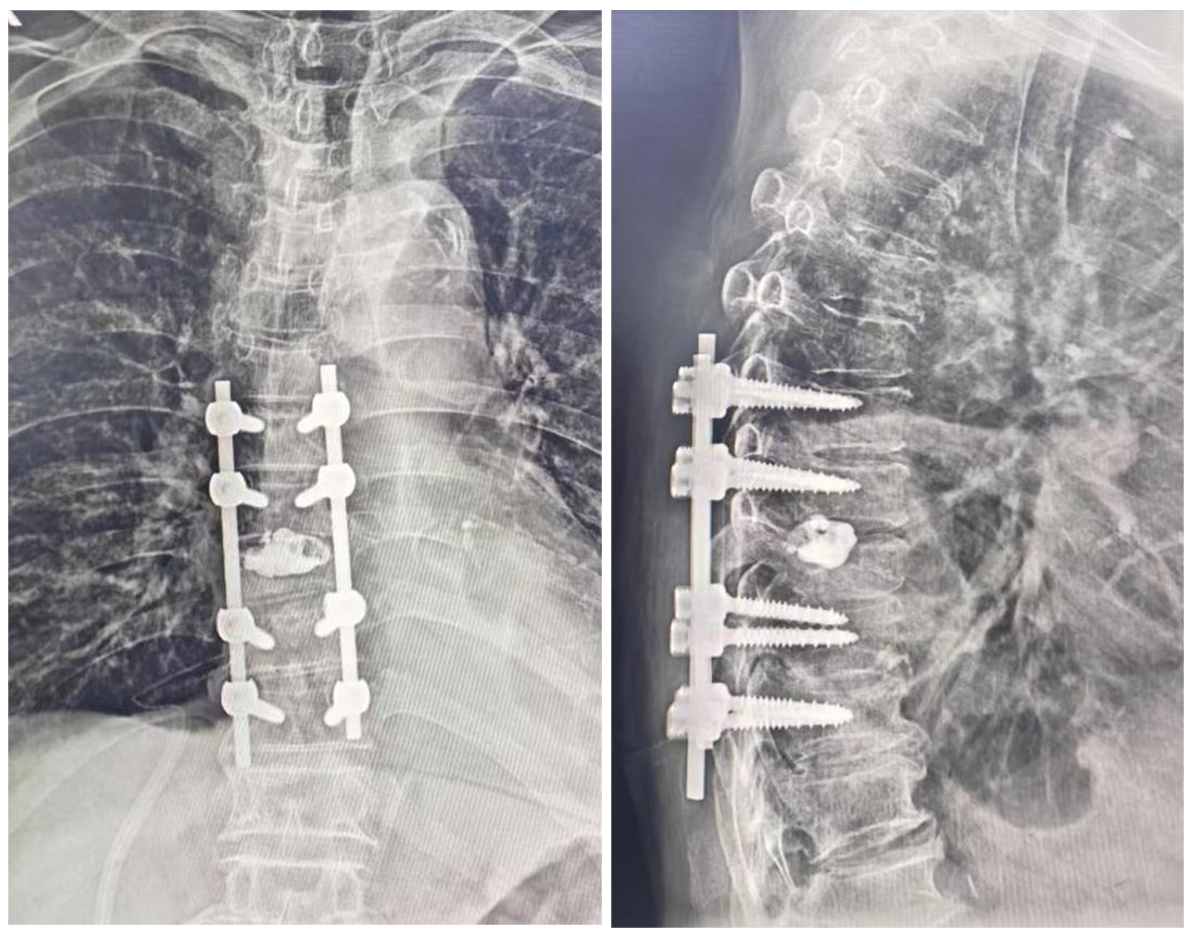

林飞跃主任医师团队为手术做了充足的准备。手术当天,由林飞跃主任医师主刀,在重症监护科叶勇主任医师、麻醉科张福清主任医师、手术室以及输血科的通力协作下,切除压迫脊髓的肿瘤组织及椎体的大部分转移瘤,将受压脊髓进行360度环形减压,并用骨水泥做了肿瘤的隔离,同时用椎弓根钉棒系统重建了脊柱的稳定性,顺利完成手术。患者顺利度过术后危险期,生命体征平稳,目前双腿肌力明显改善,已恢复部分自主活动。

术后复查X线片显示内固定在位无松动,骨水泥无渗漏